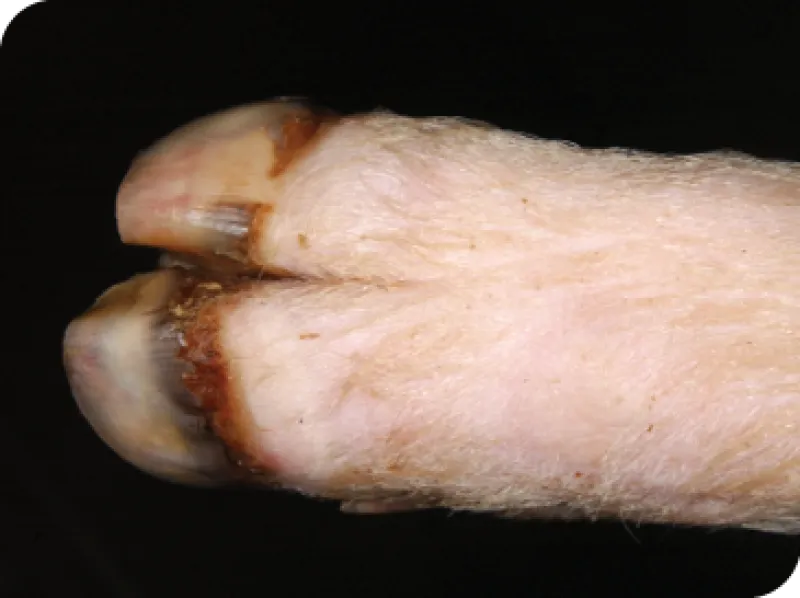

Signos de fiebre aftosa en ganado vacuno

• Ampollas y llagas: Pueden aparecer ampollas en la boca o en la lengua, en los pezones y en las pezuñas. Estas ampollas pueden romperse y dejar erosiones crudas en el tejido. Las llagas dolorosas pueden provocar síntomas adicionales, como los siguientes:

• Cojera: Los animales pueden mostrar renuencia a moverse o mostrar signos de dolor al caminar.

Los autores desean hacer un reconocimiento al Laboratorio de Diagnóstico de Enfermedades Animales Exóticas del APHIS del USDA y al Servicio de Información Visual del Departamento de Seguridad Nacional (DHS) en el Centro de Enfermedades Animales de Plum Island (PIADC), el Centro para la Seguridad Alimentaria y la Salud Pública de la Facultad de Medicina Veterinaria de Iowa State University y Rajeev Ranjan, Dirección del Proyecto sobre Fiebre Aftosa, Consejo Indio de Investigación Agrícola (lesiones en los pezones) por el uso de las imágenes de cerdos y ganado domésticos infectados por el virus de la fiebre aftosa.